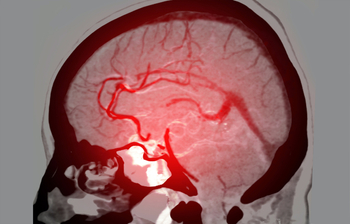

Pediatric stroke and Neurovascular abnormalities (such as Moya-Moya, AVM and arteriopathies)

Pediatric Stroke and Vasculopathy Program

MedStar Health’s Georgetown University Hospital is the only comprehensive stroke center in the Washington, D.C., area that provides specialized pediatric stroke care.

At the MedStar Health division of pediatric neurology, a team of pediatric neurologists is available 24 hours a day, seven days a week.

Our pediatric experts are skilled in the diagnosis and treatment of pediatric stroke and its multiple, underlying causes. The team includes experts in neurology; pediatric critical care; pediatric anesthesia; neurosurgery; pediatric hematology; pediatric nursing; pediatric neuroradiology; and physical, speech, and occupational therapists.

The division of pediatric neurology offers stroke clinics and spasticity clinics in our Tenleytown location to facilitate follow-up care.